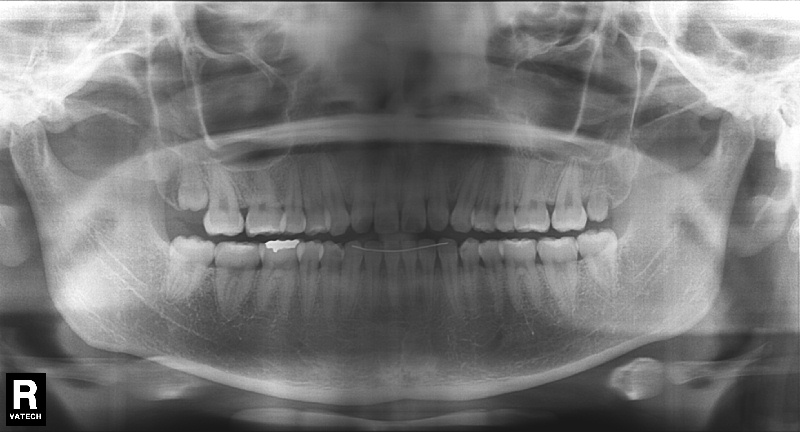

치료 전 사진입니다.